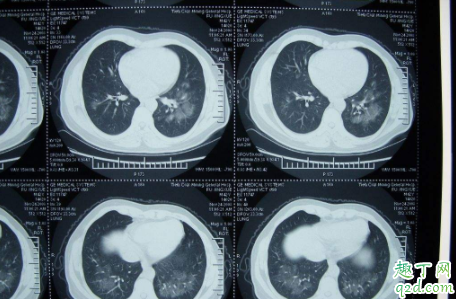

为什么一定要做更贵的CT不做胸片,以前我们怀疑病人有肺炎,会考虑拍胸片,而且胸片与CT一样,都是用X线,但是它们之间有一个差距,如果是非常轻微的,早期的肺炎,由于其影响密度只是一点点变化,在我们胸片里面是很难看出来的,甚至可以直接说就是漏诊,但是如果病人拍的是CT,就能看得出来,因为CT检查的密度分辨率是胸片的20倍左右 。